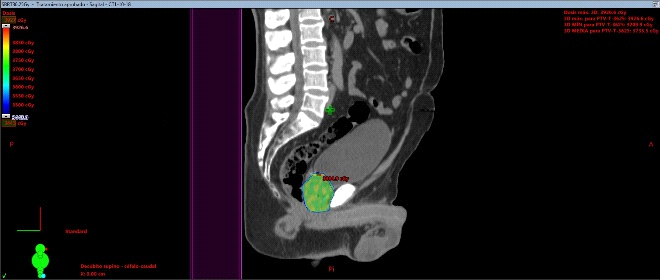

Se presentan figuras de un caso clínico de nuestro centro. Paciente de 57 años, APE: 6.5, Biopsia Gleason 7 (3+4) 2/6 sextantes. Etapificación (-), Rechaza cirugía.

Fig. 6. Tac con fiduciales y contornos. Dosimetría: 36.25Gy en 5 Sesiones, Días alternos. Los fiduciales son los puntos blancos dentro de la próstata semilla que se implantan previamente para tener un punto de referencia local confiables al realizar imágenes diaras previo al inicio de cada sesión.

Fig. 7. Dosimetría con aprobación de parámetros de dosis en Target y órganos de riesgo. Las barras verdes, evidencian que el plan de Radioterapia estereotáxica está cumpliendo con los parámetros de seguridad sobre los órganos de riesgo con la dosis adecuado sobre la próstata. Cuando aparecen barras rojas, se pasa a un segundo nivel de seguridad, en donde las dosis del target aseguran la mínima posibilidad de toxicidad sobre los OAR.